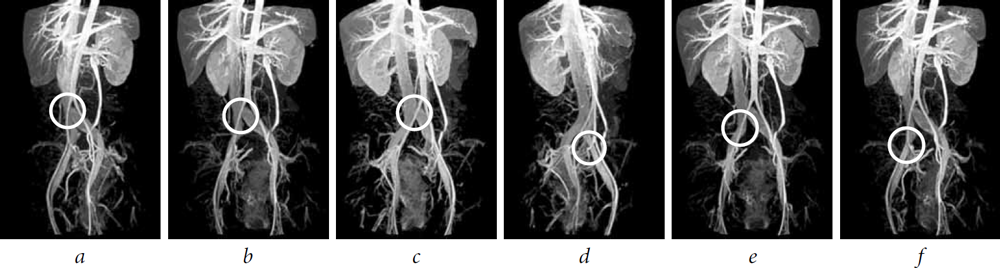

Our analysis of the MRI and CT-phlebography data, as well as X-ray contrast phlebography, enabled the proposal of our own classification of arteriovenous obstructions in the ileocaval segment:

- central proximal: high aortic bifurcation, in which the right common iliac artery compresses the lower section of the inferior vena cava before it is divided into the iliac veins (Fig. 1, a);

- central distal: high aortic bifurcation, in which the right common iliac artery compresses the lower section of the inferior vena cava at the point of its division into the iliac veins (Fig. 1, b);

- left proximal: the right common iliac artery compresses the left common iliac vein (May–Thurner syndrome) (Fig. 1, c);

- left distal: compression by the left external and/or left internal iliac artery of the left external iliac vein (Fig. 1, d);

- right proximal: compression by the right common iliac artery of the right common iliac vein (Fig. 1, e);

- right distal: compression by the right external and/or right internal iliac artery of the right external iliac vein (Fig. 1, f ).

Fig. 1. Magnetic resonance imaging of the inferior vena cava and small pelvic vessels: (a) central proximal arteriovenous obstruction of the ileocaval segment; (b) central distal arteriovenous obstruction of the ileocaval segment; (c) left proximal arteriovenous obstruction of the ileocaval segment or May–Thurner syndrome; (d) left distal arteriovenous obstruction of the ileocaval segment; (e) right proximal arteriovenous obstruction of the ileocaval segment; and (f) right distal arteriovenous obstruction of the ileocaval segment (modeling)

The central proximal arteriovenous obstruction of the ileocaval segment was detected in 4 patients (6.1%), central distal arteriovenous obstruction was noted in 7 patients (10.6%), left proximal obstruction was seen in 52 patients (78.8%), left distal arteriovenous obstruction was seen in 31 patients (47%), right proximal obstruction was seen in 1 patient (1.5%), and right distal arteriovenous obstruction was seen in 1 patient (1.5%). Various combinations of arteriovenous obstructions in the ileocaval segment were revealed in 32 (48.5%) of 66 patients (Fig. 2).